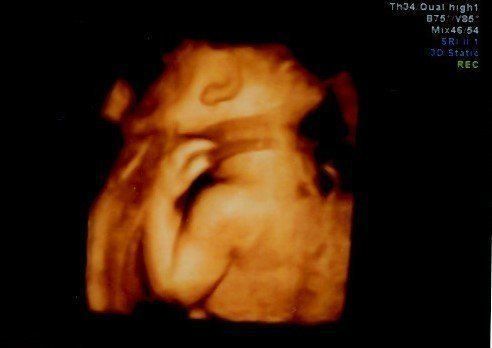

妊娠29週目のエコー写真 3Dのエコー画像撮影にチャレンジ

わざわざ別の産院に出向き、高い料金を払って3D画像撮影に挑んだものの、なんと、撮影した時間帯の赤ちゃんはおなかに向かって後ろ向きにおねんね中。残念ながら期待していたような顔がわかる3D画像は撮影できませんでした。それでも、2D画像ではわからなかった腕や後ろ姿が鮮明に写っており、とても興奮しました。